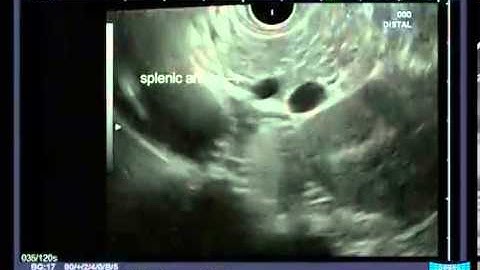

UNDERSTANDING REDIAL EUS SCOPE